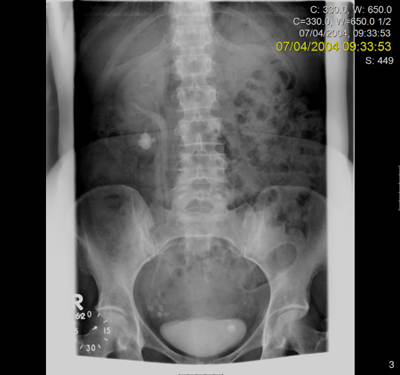

Marking for PCNL access.

PCNL was discussed at a specialist x-ray meeting but considered unsafe due to the risk of perforating overlying bowel.

A right sided transperitoneal laparoscopic approach was utilised, sweeping ascending colon medially. The renal pelvis was incised and stones were removed using a flexible cystoscope and the renal pelvis was closed over a stent.